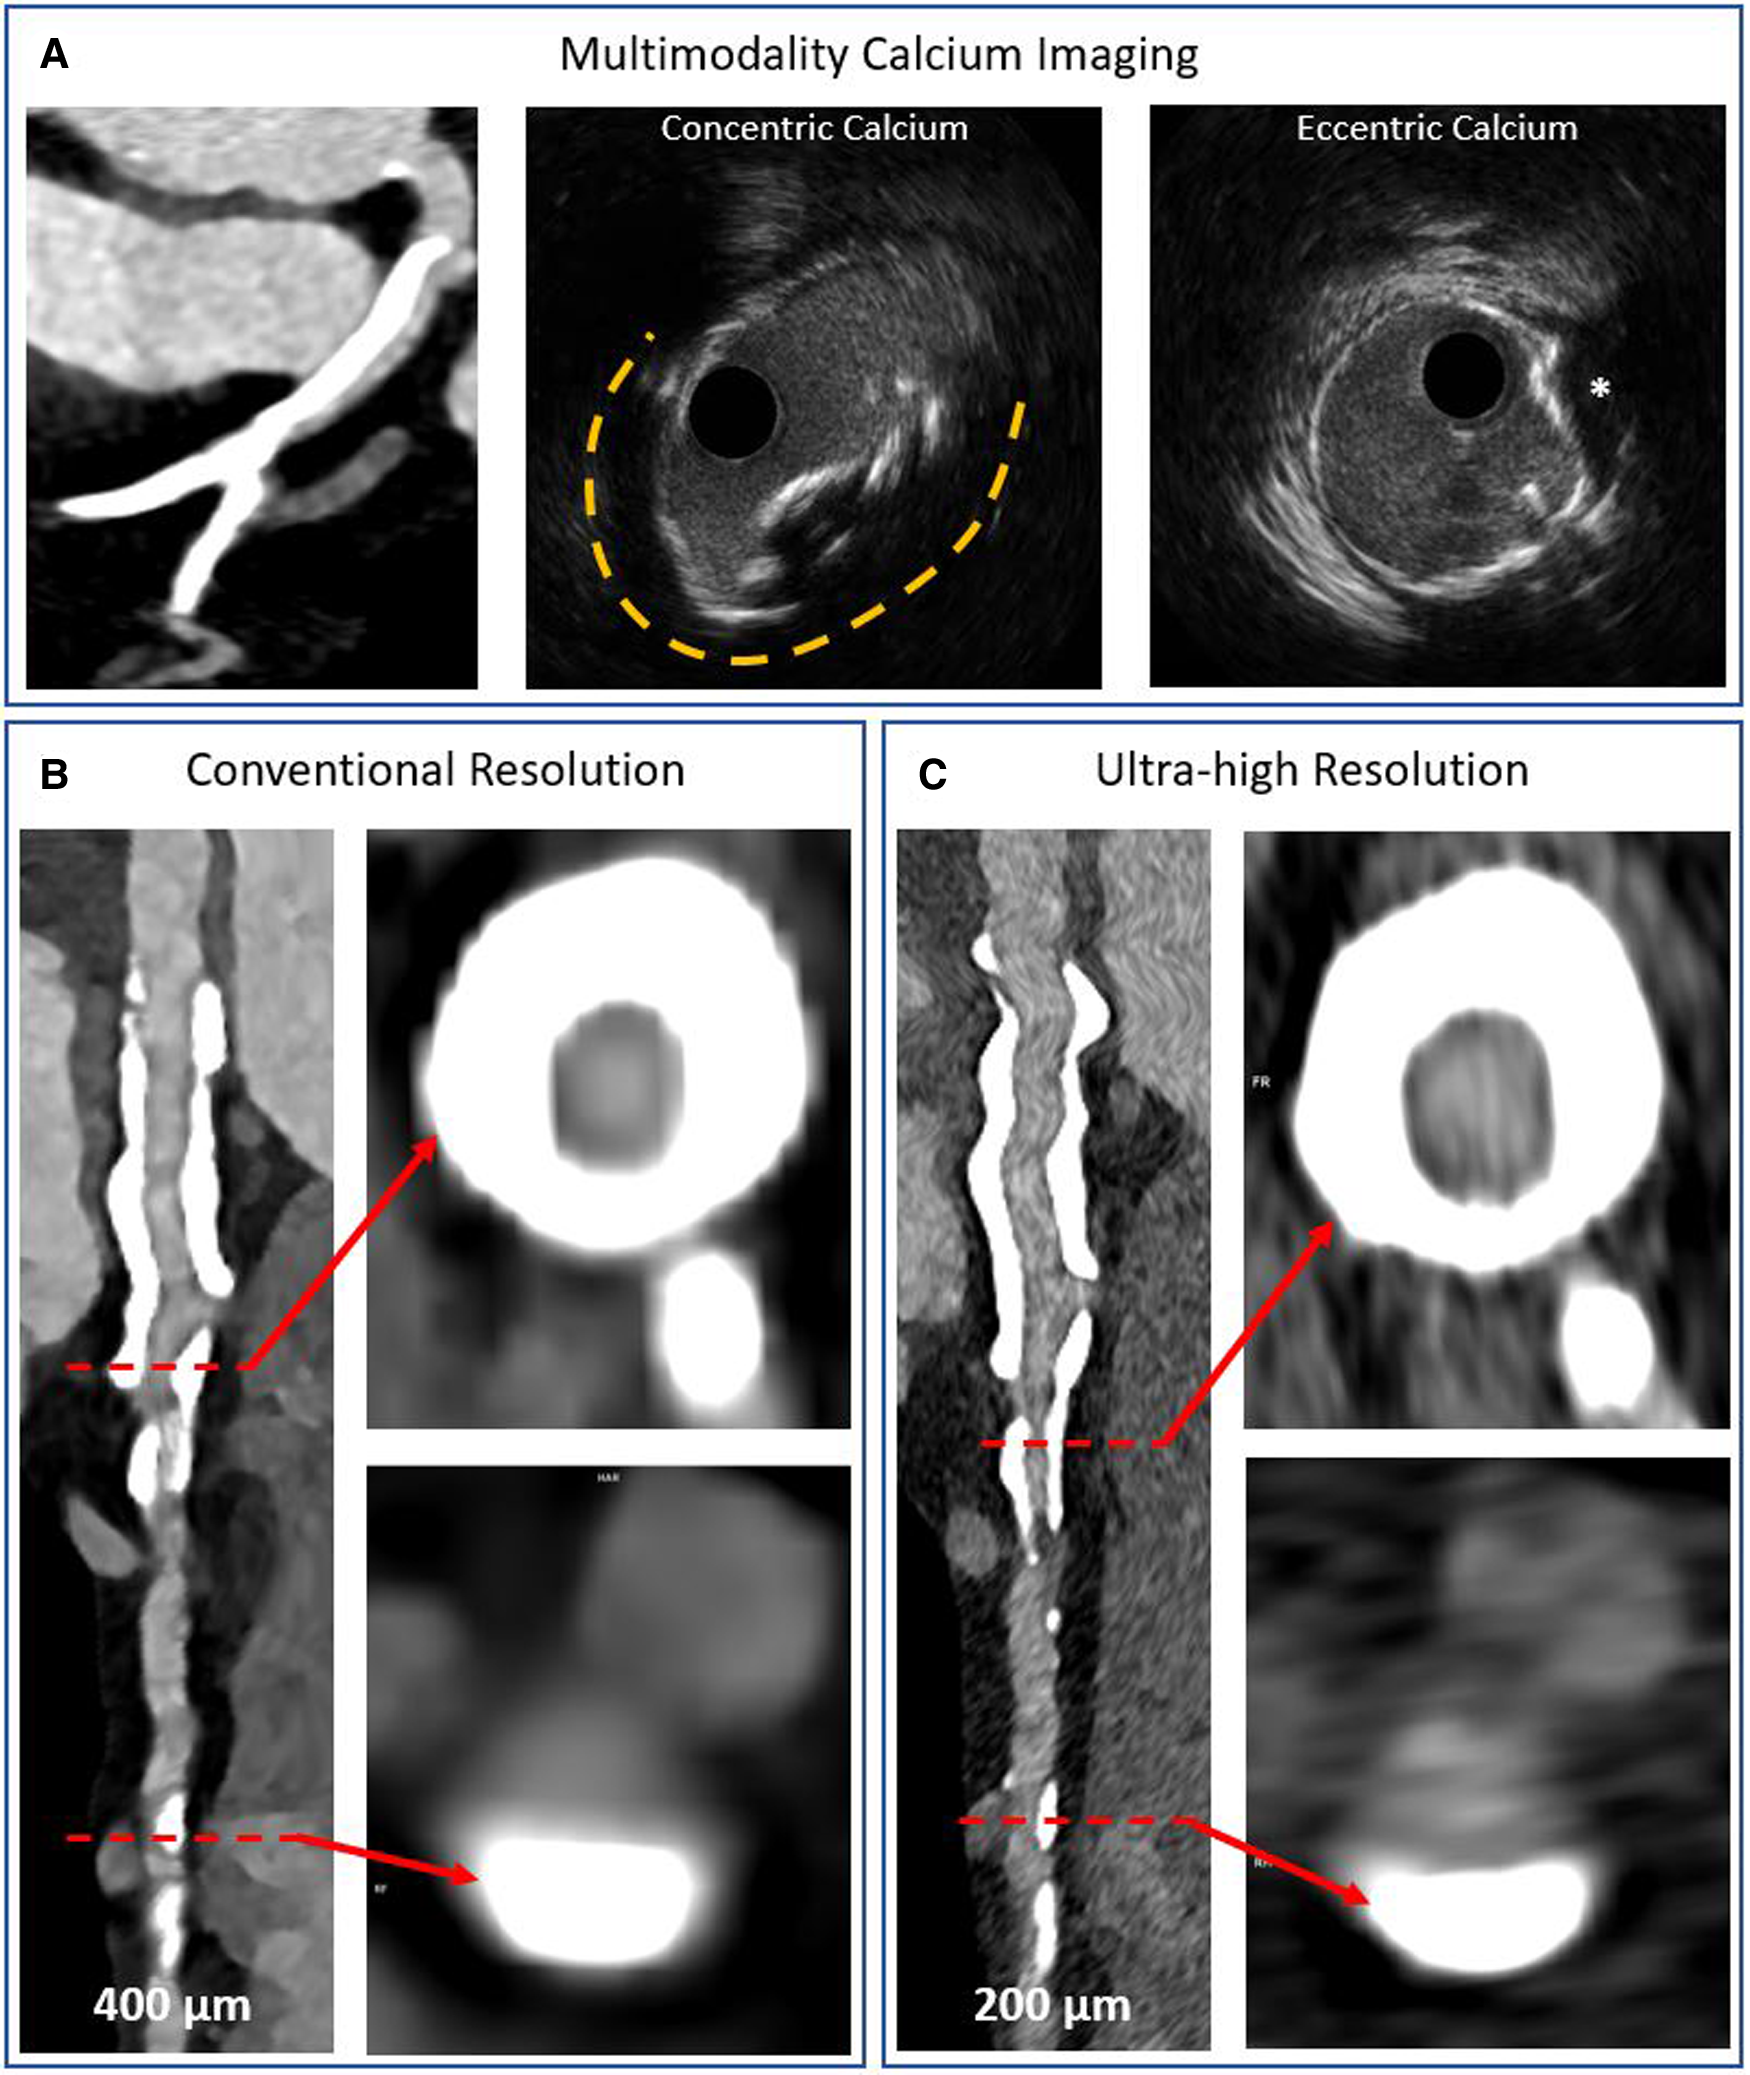

A further step forward in CCTA-based characterization of CAC might come from the recent introduction of photon-counting (PC) detector technology in CT scanning. PC CT imaging offers high temporal (66 milliseconds) and spatial (130 micrometers) resolution and multi-energy acquisitions that have improved its spectral resolution (41). The anticipated improvement in feature detection and material quantification will allow the selective isolation of different materials (e.g., calcium, iodinated contrast) and lead to more accurate calcium characterization (thickness), reduction of blooming artifacts, and superior luminal stenosis evaluation (42, 43). The first imaging systems have been installed and although early-stage, clinical experience is promising (Figure 8).

Figure 8

Multimodality imaging of calcified coronary arteries. Panel A shows a heavily calcified coronary artery segment on conventional detector CT imaging and intravascular ultrasound imaging examples of concentric and eccentric calcification patterns. The asterisk denotes a calcium nodule. Panels B,C show photon counting CT acquisitions of a heavily calcified vessel with concentric and eccentric calcification patterns at conventional and ultra-high resolutions, respectively. The blooming artefact is reduced while the lumen is more clearly visualized in the ultra-high resolution acquisition.